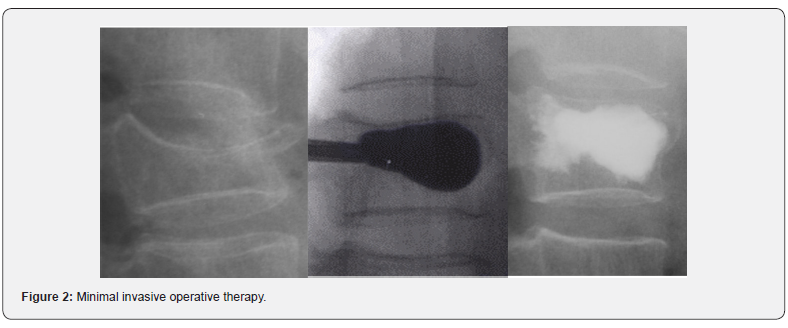

Kyphoplasty and vertebroplasty are minimally invasive percutaneous procedures. In the case of vertebral fractures, cement is applied to one or both pedicles under radiological monitoring [8]. In contrast to vertebroplasty, kyphoplasty involves the initial insertion of a balloon. The balloon is expanded to produce a cavity which is filled with bone cement [9] (Figure 2).

The objectives of balloon kyphoplasty are to restore the original height of the fractured vertebra and to counteract the progressive deformation of the spine along the sagittal plane, in other words, the kyphosis in the thoracic area [10]. Another advantage of balloon kyphoplasty is the fact that, by creating a cavity, cement can be instilled in the vertebra using a significantly lower level of injection pressure, which makes it less likely that cement will leak [11].